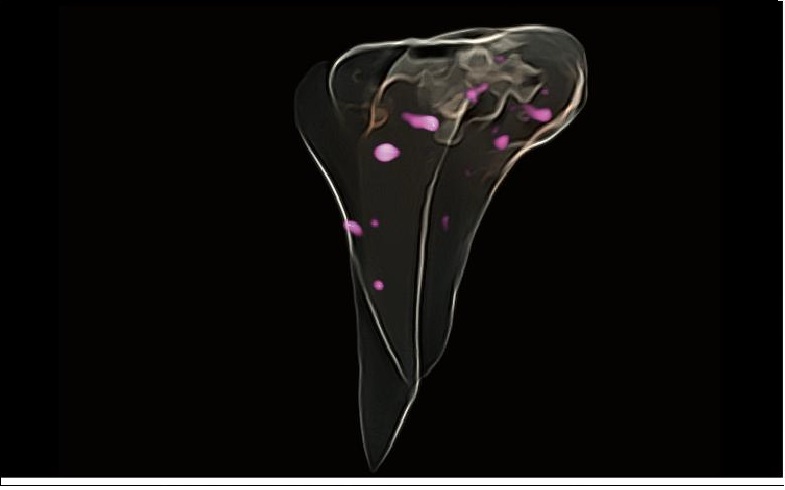

SONO FUSION

Prob içerisine entegre edilmiş manyetik sensör sayesinde, SonoFusion harici bir manyetik sensör ihtiyacını ortadan kaldırır ve ultrason verilerini BT/MR verileriyle birleştirerek görüntü eşleştirme yoluyla eşzamanlı gösterim sağlar. Bu entegrasyon, klinisyenlerin hastalıkları kapsamlı bir şekilde analiz etmesini kolaylaştırır.